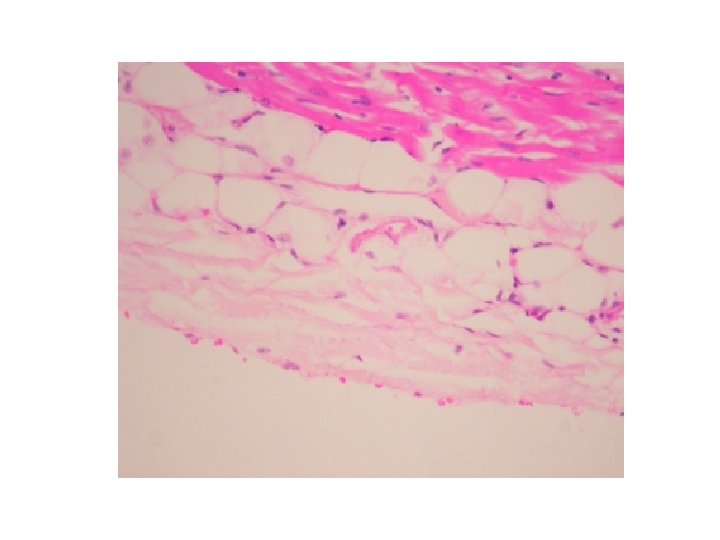

EPICARDIO • La capa mas externa de la pared del corazón, también se denomina capa visceral del pericardio (compuesta por un epitelio escamosos simple conocido como mesotelio).

• La capa subepicárdica de tejido conectivo laxo contiene vasos coronarios, nervios y ganglios. En las raíces de los vasos que penetran y salen del corazón el pericardio visceral se continúa con la capa serosa del pericardio parietal (en raíces de vasos). • Estas dos capas del pericardio encierran la cavidad pericárdica (espacio con cantidad pequeña de líquido seroso para lubricar la capa serosa del pericardio y pericardio visceral).